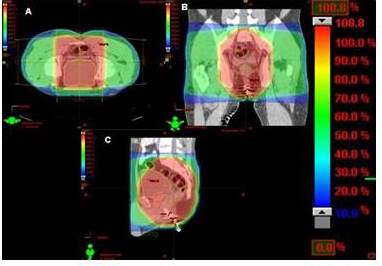

En cuanto a la RT, la técnica más utilizada fue la conformada con planificación tridimensional (RTC 3D), sólo en 3 pacientes se empleó la técnica de intensidad modulada (RTIM). Se utilizaron 4 campos, dos laterales, uno anterior y otro posterior, que inicialmente incluían toda la pelvis, con fracciones diarias de 180-200 cGy hasta una dosis de 4 500-4 600 cGy, realizando posteriormente reducción al sitio de lesión macroscópica (RT neoadyuvante) o al área de anastomosis (RT adyuvante) hasta completar 5 000-5 040cGy (Cuadro 1 y Figura 1-4).